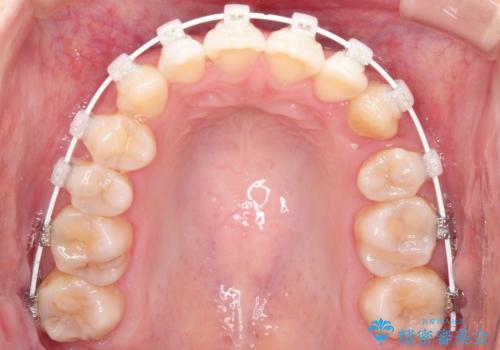

装置は表側のワイヤーを選択されました。

ガタガタがなくなり、上下の前歯が接触すようになり、見た目とともに咬みやすくすることができました。